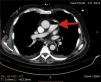

A 72-year-old man, previously independent, was admitted to the emergency department following cardiorespiratory arrest. A chest computed tomography scan (CTS) was requested. During the exam, the patient experienced sudden hypotension (65/20¿;mmHg) and poor peripheral perfusion. The exam was suspended and a fluid bolus was administered, resulting in transient reversal of the condition. Gas was detected in the injection system, which was replaced, and the exam was repeated. The CTS revealed gas embolism with an air-fluid level in the main pulmonary artery (marked with an arrow in Fig. 1), right atrium and right ventricle (marked with an arrow in Fig. 2), as well as in the left upper lobar artery (marked with an arrow in Fig. 3). Due to the venous gas embolism, he was transferred for treatment at a hyperbaric medicine center.